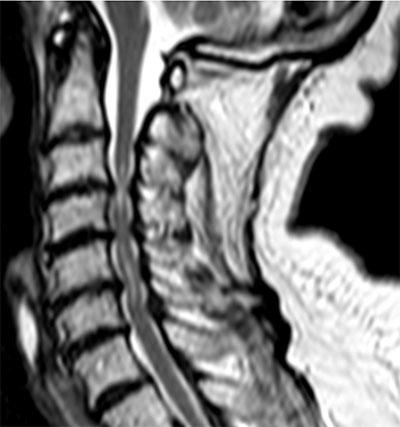

Diskproteser ger bättre funktion, mindre smärta och färre komplikationer än 1: fusion, 2: dekompression, eller 3: ingen kirurgisk behandling alls.

Kyfoplastik/vertebroplastik ger bättre långtidsresultat (smärta, värk, funktion) vid behandling av osteoporotiska kotfrakturer än konservativ behandling. (En hel del talar för att denna hypotes är svag eftersom metoden nu används i betydligt mindre utsträckning än i samband med dess entusiastiska introduktion. En kommersiell framgång har det dock varit).

Brosktransplantation vid broskskador i stora leder minskar risken för artros.

Höftledsartroskopi, med eller utan intervention, är en säker metod som inte ökar risken för degenerativa förändringar och som tillför diagnostisk information utöver vad som kan fås med icke-invasiva metoder.

Så nog finns det att göra!

Hypotes: genom att göra en artroris (skruva in en titanskruv mellan talus och calcaneus) kan fotens längsgående fotvalv återställas